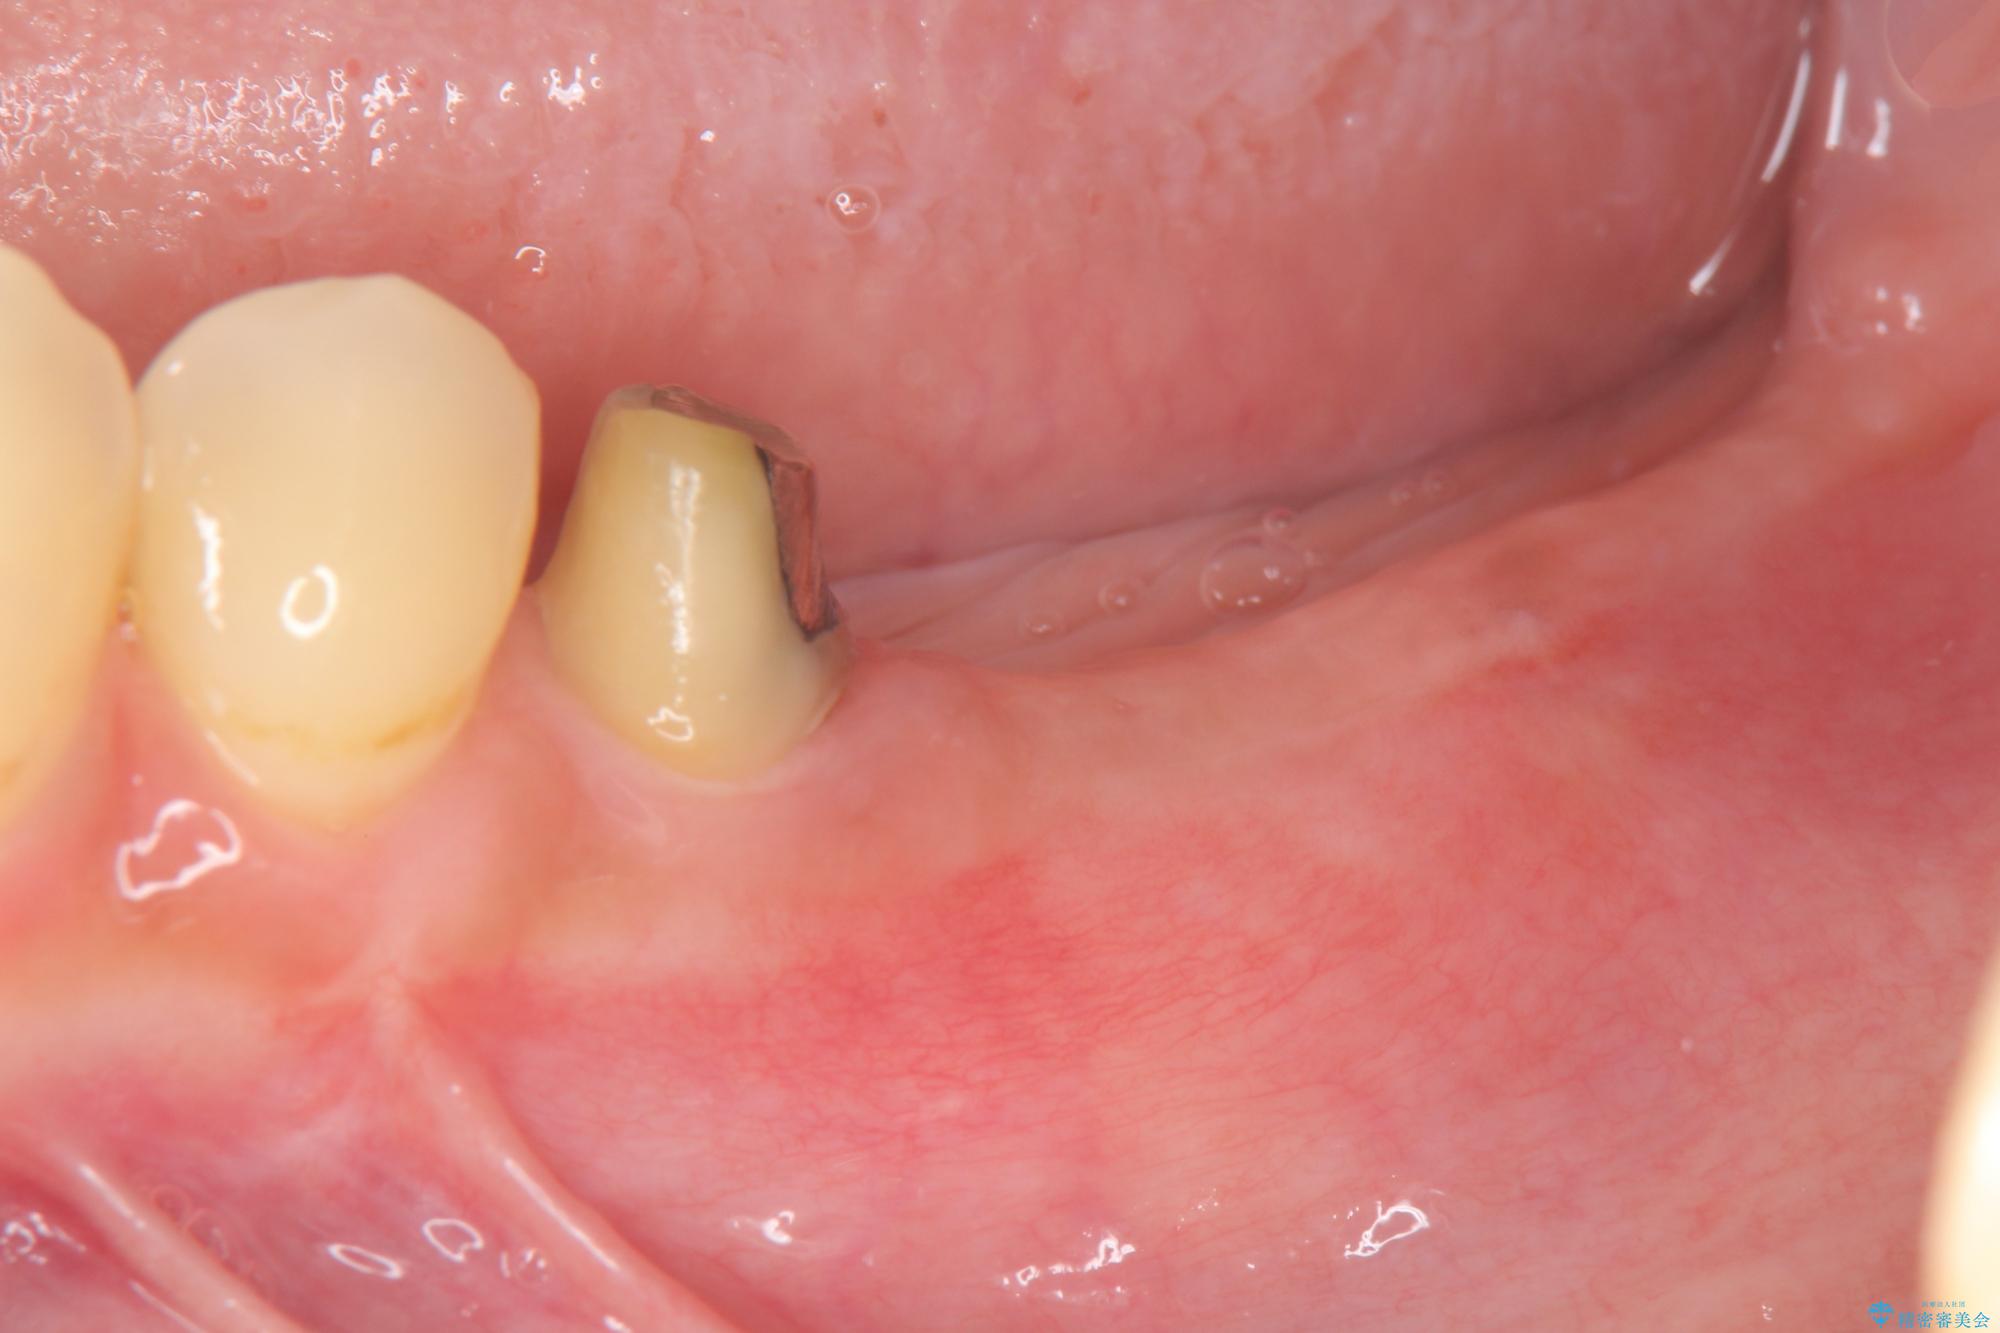

- 他院で根の治療まで終え、違和感が取れず相談に来院されました。

当該歯を精査したところ、歯根に破折が見られ抜歯を余儀なくされました。